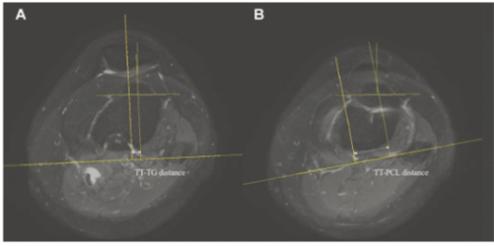

물리치료나 보조기 착용 등 보존적 치료에도 탈구가 반복되면 수술을 고려하게 된다. 성인의 경우 경골결절(정강이뼈에서 가장 튀어나온 부분)과 활차구 사이(TT-TG) 및 경골결절과 후방십자인대 사이(TT-PCL) 거리를 측정해 TT-TG 거리 20mm 또는 TT-PCL 거리 24mm을 기준으로, 이보다 큰 경우 심각한 불균형이 있다고 판단하고 슬개골을 제자리에 되돌려놓는 ‘원위부 재정렬 수술’을 하게 된다.

이에 분당서울대병원 정형외과 성기혁 교수 연구팀은 20세 이하 소아·청소년 596명의 무릎 MRI를 대상으로 연령대별 TT-TG 및 TT-PCL 거리의 정상 값과 슬개골 불안정성 위험을 예측하는 기준 값을 알아보고자 연구를 진행했다.

그 결과, 87명이 불안정성군, 509명이 불안정성이 없는 정상군에 속했는데 이 중 정상군에 속한 소아의 TT-TG 거리는 8.2mm, TT-PCL 거리는 19.5mm였다. 이는 불안정성군의 TT-TG 및 TT-PCL 거리인 16.1mm와 24.4mm와 비교해 짧았다. 또한, 정상군에 속한 소아·청소년의 TT-TG 및 TT-PCL 거리는 각각 15세, 11세까지 매년 증가하는 것을 확인할 수 있었다.

또한, 연구팀은 분석을 통해 소아·청소년의 TT-TG 거리 14.9mm, 또는 TT-PCL 거리 23.7mm를 슬개골 불안정성 위험이 높아지는 기준 값으로 제시했다. 이는 소아·청소년의 TT-TG 및 TT-PCL 거리를 측정해 연구팀이 제시한 기준 값보다 클 경우 뼈의 구조를 교정하기 위한 수술적 치료를 고려해야 함을 의미한다.